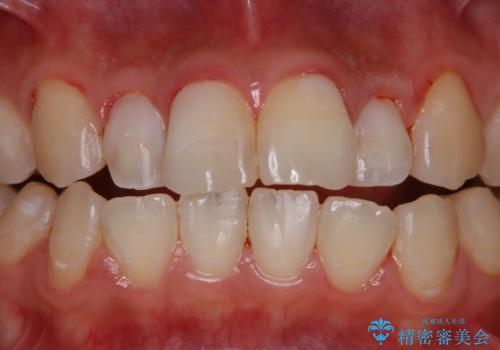

歯面がバイオフィルム(細菌の塊)や歯石で覆われていました。

PMTC(自費クリーニング)で、専門的な器具を使用し、歯石を砕き、バイオフィルムを剥がし、トリートメントまで行いました。歯肉が腫れていたため、バイオフィルムや歯石を取り除いたことにより、施術後の歯肉から出血が見られます。ただし、出血は次第におさまります。

PMTC(自費クリーニング)はホワイトニングではないため、歯が白くなることはありませんが、徹底的に汚れを除去しますので、ご自身本来の歯面となり、艶がでて明るい印象となります。